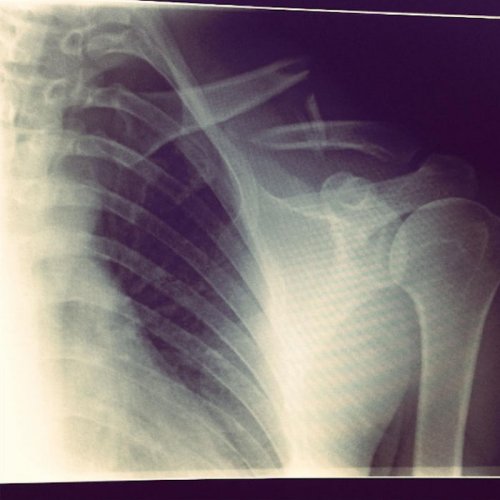

Все началось с первой лыжной поездки прошлого зимнего сезона 2015-2016. Чтобы отпраздновать выезд Клеменс решил сходу сделать сальто на снегу. Сразу же после трюка парень попал в больницу со сломанной ключицей и четырьмя треснувшими ребрами. Не лучший день в его жизни…

Через три дня Злами выписали с кипой рентгеновских снимков и шрамом. Металлическая пластина провела целый год в теле лыжника, чтобы кости срослись правильно и надежно. Кстати, в аэропорту Берлина у парня из-за этого однажды были проблемы на плановом досмотре металлодетектором.